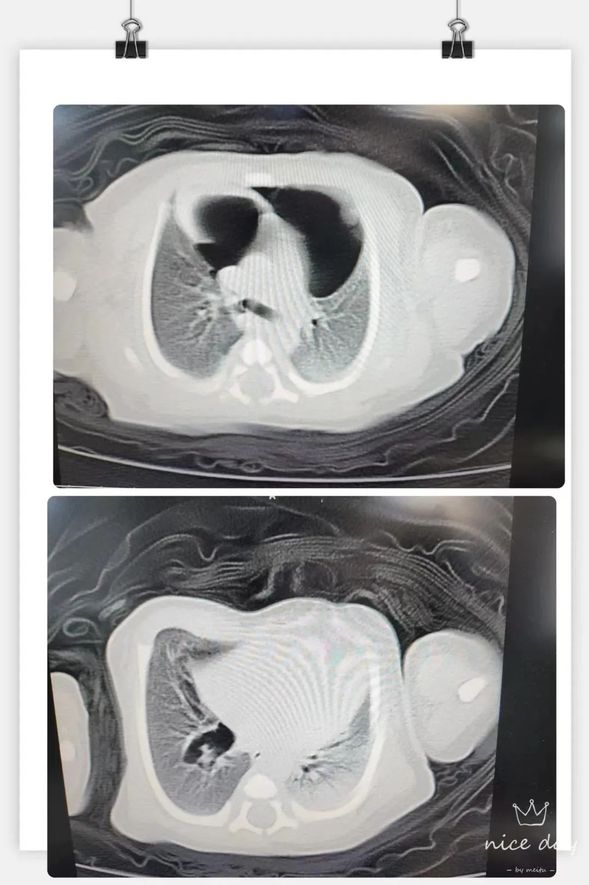

患儿纵隔气肿CT影像

入院的第2天,医生发现患儿突然出现呼吸困难加重,烦躁不安,哭闹不易安抚,综合评估后不除外气漏综合征可能。于是立即完善胸部CT检查,由于患儿需呼吸机辅助呼吸,CT检查只能在持续复苏囊加压给氧下完成,夜班胡世娇医生考虑患儿病情危重,置身陪同患儿完成检查,虽冒着被放射性辐射的风险,却义无反顾。CT显示患儿双肺透亮度进一步下降,通气功能障碍,双肺内炎性病变严重,并出现了大量纵膈气肿,右肺下叶可见气囊腔暂不除外先天发育异常,病情变得复杂起来。